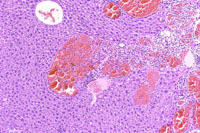

A hemangioma has destroyed the normal hepatic parenchyma. A thrombus is present at the top of the hemangioma; high magnification shows dilated vascular channels lined by flattened endothelial cells. There is minimal atrophy of hepatic cords.